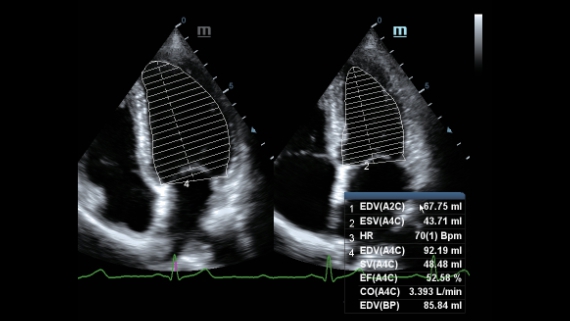

–ú–Ω–æ–≥–æ—Ñ—É–Ω–∫—Ü–∏–æ–Ω–∞–ª—å–Ω–∞—è —Å–∏—Å—Ç–µ–º–∞ DC-60 Exp —Å X-Insight –ø—Ä–µ–¥—Å—Ç–∞–≤–ª—è–µ—Ç —Å–æ–±–æ–π –∫–æ–º–ø–ª–µ–∫—Å–Ω–æ–µ —Ä–µ—à–µ–Ω–∏–µ, –∫–æ—Ç–æ—Ä–æ–µ –ø–æ–º–æ–≥–∞–µ—Ç —É–ø—Ä–∞–≤–ª—è—Ç—å –ø–æ–≤—Å–µ–¥–Ω–µ–≤–Ω–æ–π –∫–ª–∏–Ω–∏—á–µ—Å–∫–æ–π –ø—Ä–∞–∫—Ç–∏–∫–æ–π —Å –ª–µ–≥–∫–æ—Å—Ç—å—é –∏ —É–≤–µ—Ä–µ–Ω–Ω–æ—Å—Ç—å—é.

–û—Å–Ω–æ–≤—ã–≤–∞—è—Å—å –Ω–∞ –≥–ª—É–±–æ–∫–æ–º –ø–æ–Ω–∏–º–∞–Ω–∏–∏ –ø–æ—Ç—Ä–µ–±–Ω–æ—Å—Ç–µ–π –∫–ª–∏–µ–Ω—Ç–æ–≤, –∫–æ–º–ø–∞–Ω–∏—è Mindray —Ä–∞–∑—Ä–∞–±–æ—Ç–∞–ª–∞ —Å–∏—Å—Ç–µ–º—É DC-60 Exp —Å X-Insight, —á—Ç–æ–±—ã –æ–±–µ—Å–ø–µ—á–∏—Ç—å –≤—ã—Å–æ–∫—É—é –ø—Ä–æ–∏–∑–≤–æ–¥–∏—Ç–µ–ª—å–Ω–æ—Å—Ç—å –∏ —Ç–æ—á–Ω–æ—Å—Ç—å –≤–∏–∑—É–∞–ª–∏–∑–∞—Ü–∏–∏ –≤–∫—É–ø–µ —Å –Ω–∞–≥–ª—è–¥–Ω–æ—Å—Ç—å—é, –∏—Å–∫–ª—é—á–∏—Ç–µ–ª—å–Ω–æ–π –∏–Ω—Ç–µ–ª–ª–µ–∫—Ç—É–∞–ª—å–Ω–æ—Å—Ç—å—é –∏ –æ–≥—Ä–æ–º–Ω—ã–º –æ–ø—ã—Ç–æ–º.